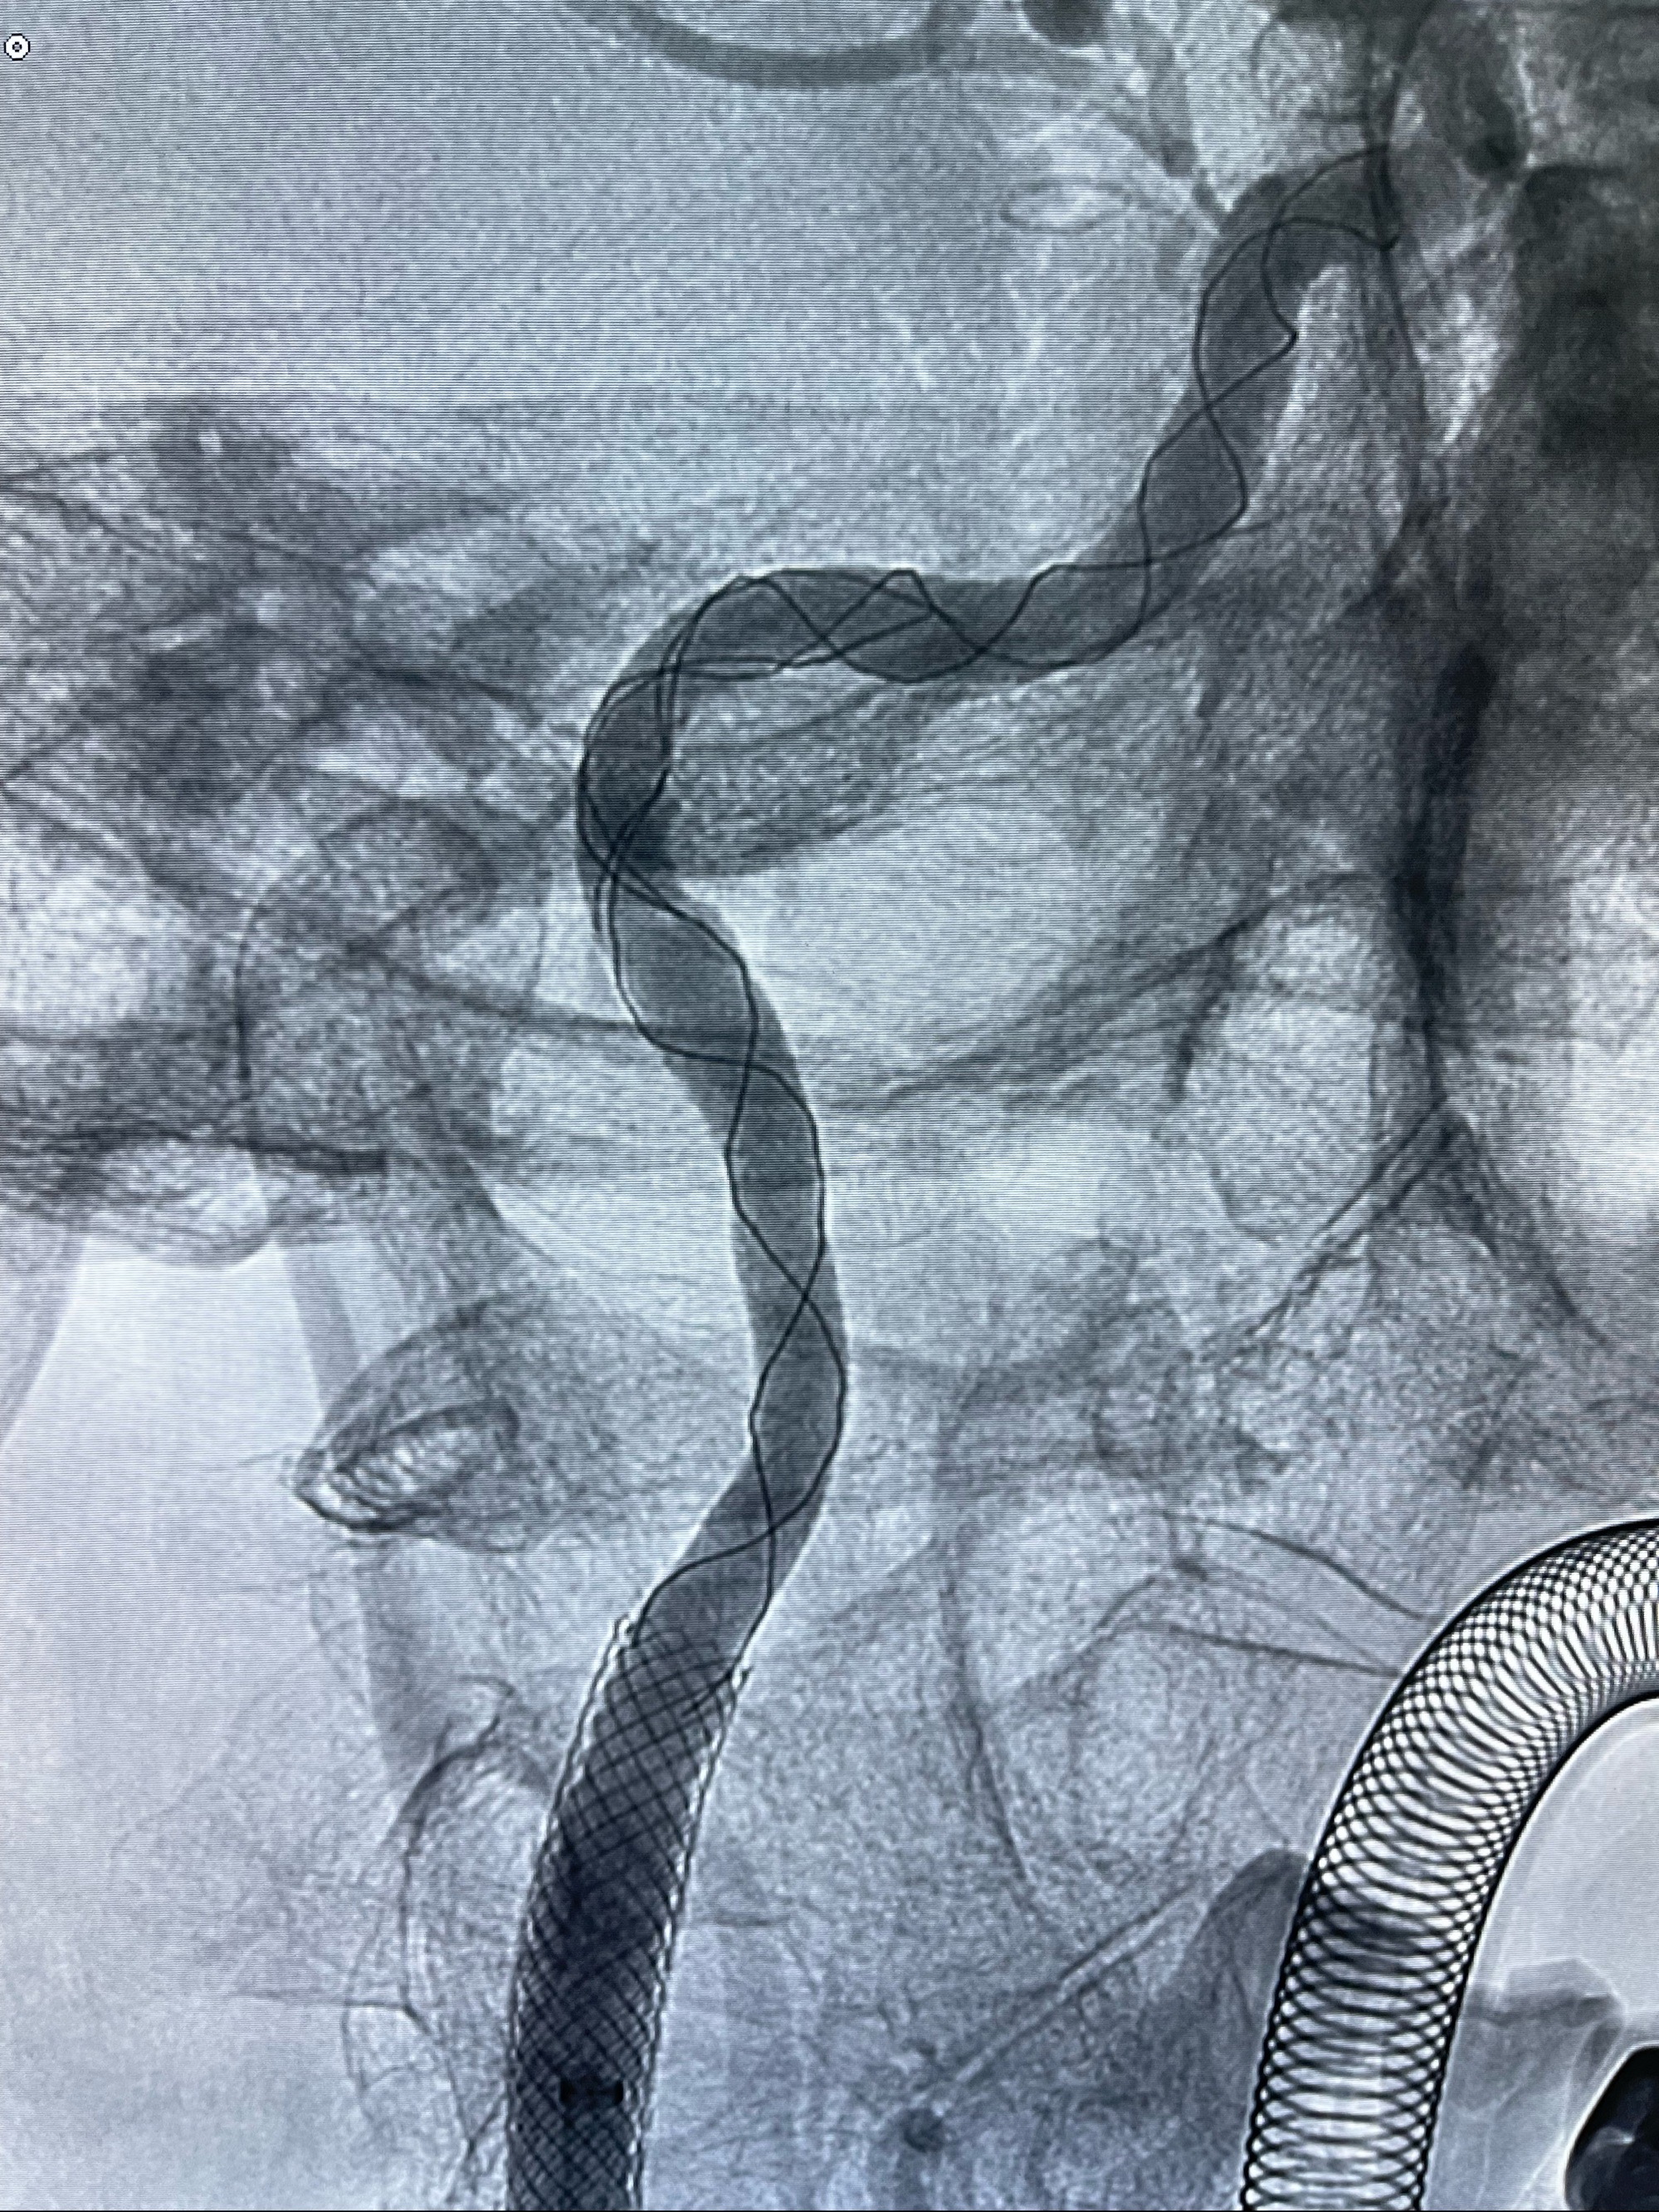

重新行“路径图”,支架导管在微导丝引导下超选择性插入至右侧颈内动脉眼段,4.5-50mmLeo支架释放,远心端位于海绵窦段,近心端位于岩骨段狭窄段以近

即刻造影显示支架贴壁佳

路径图下,5.5-50mmLeo支架导管在微导丝引导下超选择性插入远段Leo支架内

两枚支架部分重叠

多次确认支架位置及打开贴壁情况

支架完全打开,近心端位于原颈动脉支架远心端内